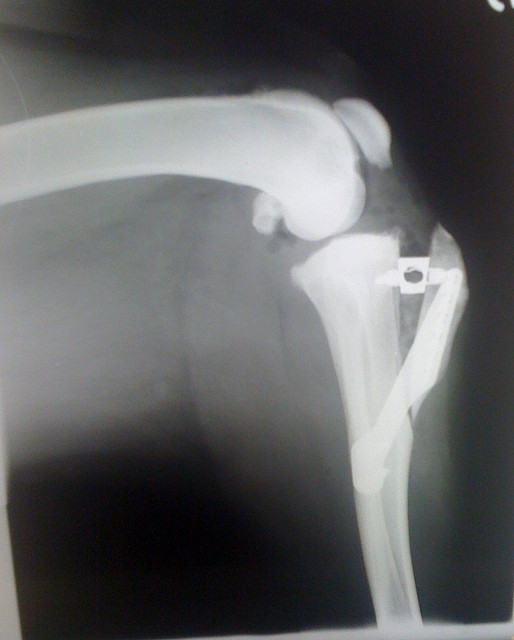

Knee X-Ray

Date:

8/22/14